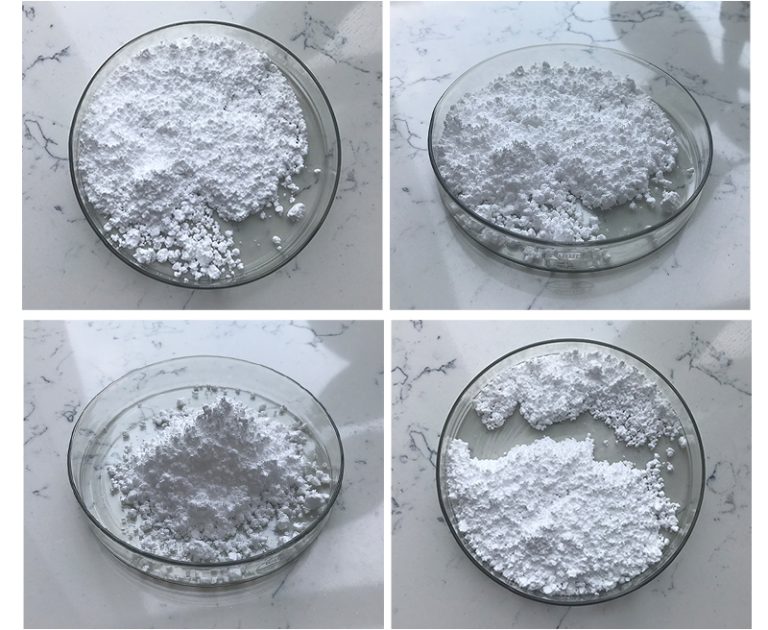

Citicoline sodium (also known as CDP-choline) is a compound that plays a…

Citicoline sodium (also known as CDP-choline) is a compound that plays a…

Citicoline Sodium (also known as CDP-Choline) is a supplement that is often…

Citicoline sodium, also known as CDP-choline (cytidine 5′-diphosphocholine), is a compound that…

Citicoline sodium (also known as CDP-choline sodium or cytidine diphosphate choline sodium)…

Citicoline Sodium, also known as CDP-Choline (cytidine diphosphate choline), is a nootropic…

Citicoline sodium (also known as sodium cytidine 5′-diphosphocholine or CDP-choline) is a…

Citicoline Sodium, also known as cytidine diphosphate-choline (CDP-choline), is a compound that…